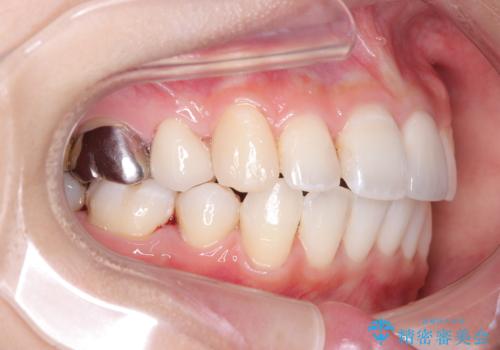

- 口元が出ていることを気にされて来院されました。精密な検査の結果、歯列全体のスペースが不足していることが判明。患者様のご希望である「口元を下げたい」というご要望を叶えるため、上下左右の小臼歯を抜歯し、そのスペースを利用して前歯を奥へ移動させる治療計画を立案しました。また、仕事上、目立つ矯正装置を避けたいというご希望から、上顎に裏側矯正、下顎に表側矯正を組み合わせたハーフリンガル矯正を提案しました。

今回の矯正治療では、口元を大きく下げるため、上下左右の小臼歯を抜歯しました。装置には、上顎は歯の裏側に装着する裏側矯正(舌側矯正)を、下顎は透明で目立ちにくい審美ブラケットを使用するハーフリンガル矯正を選択。これにより、治療中も他人の目を気にすることなく、ストレスなく過ごしていただけました。抜歯によってできたスペースを有効活用し、歯列全体を後方へ移動させることで、口元の突出感を解消。治療の結果、口元がすっきりと整い、自信のある美しい横顔を獲得していただけました。